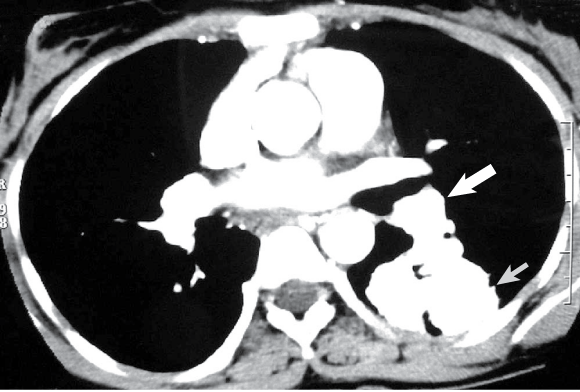

On examination, the patient had cyanosis and clubbing (Box 1), and a lumpy tongue (Box 2) suggestive of tongue telangiectasia. A chest x-ray showed left mid-zone opacity (Box 3), which was confirmed to be a pulmonary arteriovenous malformation (AVM) on spiral computed tomographic angiography (Box 4). Transcutaneous embolotherapy produced a marked improvement in her symptoms. The patient is currently asymptomatic and undergoing regular follow-up.

The patient has hereditary haemorrhagic telangiectasia (Osler–Weber–Rendu disease), an autosomal dominant disorder related to mutations on chromosomes 9 and 12. Clinical diagnosis is based on the findings of epistaxis, telangiectasia, visceral AVMs and family history. Fulfilling three of these criteria indicates a definite diagnosis; two, a possible case. In our patient, the presence of three of the four manifestations confirmed the diagnosis.

Pulmonary AVMs are found in 14%–30% of patients with this disease.1 A family history of the disease may not be present in all cases, owing to de-novo germline mutations. As these occur more frequently in later cell divisions during gametogenesis, siblings are rarely affected.